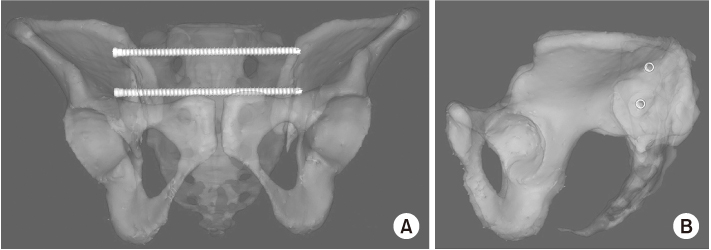

Fig. 1

(A, B) Sacral dysmorphism represents the acute angulation of sacral ala and reduced the corridor for iliosacral screw fixation. *Cortical perforation of screw.